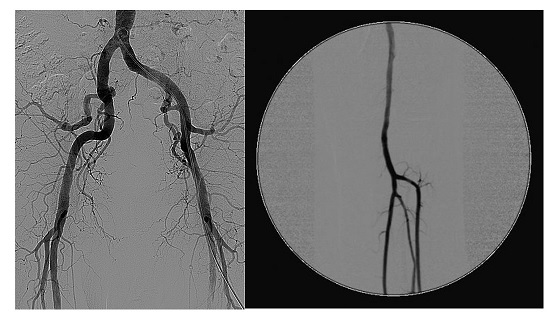

Angiografia periferica

Permette di diagnosticare malattie delle arterie che portano sangue:

- alle gambe (aorta, arterie iliache, arterie femorali, arterie poplitee e arterie tibiali)

- al cervello (arterie carotidi e arterie vertebrali)

- agli arti superiori (arterie succlavie)

- ai reni (arterie renali)

- all’intestino (arterie mesenteriche)